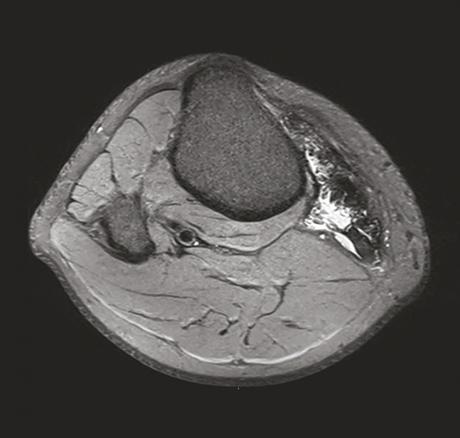

Ce jeune homme de 20 ans consultait pour une douleur du genou évoluant depuis 1 an initialement étiquetée bursite. Un traitement médical lui avait été prescrit pour cette affection. Devant la persistance de la douleur, une échographie était réalisée qui montrait une formation kystique atypique car mal limitée, à paroi épaissie et hyperhémique. Le caractère particulier de cette lésion amenait à prescrire une imagerie par résonance magnétique (IRM) qui montrait une infiltration évoquant une synovite villonodulaire en regard de l’insertion des muscles de la patte d’oie (fig. 1 et 2 ). La lésion était réséquée chirurgicalement et l’examen anatomopathologique notait une prolifération de cellules mononucléées ovoïdes ou comportant des inflexions fusiformes, associées à des histiocytes spumeux et du pigment hémosidérinique, sans atypie cytononucléaire ni activité mitotique, confirmant le diagnostic.

La synovite villonodulaire est une affection articulaire rare, focale ou diffuse, caractérisée par une hyperplasie villeuse ou nodulaire de la synoviale touchant principalement le genou et la hanche ; son étiopathogénie reste discutée. L’histoire naturelle de la forme diffuse, son caractère agressif ainsi qu’une composante génétique lui confèrent un aspect pseudotumoral qui la différencie de la forme locale. La symptomatologie est peu spécifique et entraîne un retard diagnostique. L’IRM fait le diagnostic (à condition d’y penser et de le préciser au radiologue). Le traitement de la forme focale est simple, son pronostic très bon, avec un taux de récidive faible. La forme diffuse impose une prise en charge plus radicale avec un taux de récidive élevé.1 Un traitement adjuvant ainsi qu’une surveillance sur le long terme sont recommandés. Des données récentes montrent l’intérêt de nouveaux traitements par immunothérapie, dont les modalités pratiques sont encore discutées.2